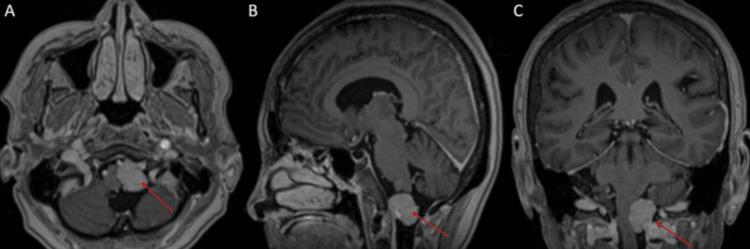

This report outlines the successful excision of an anterolateral foramen magnum meningioma (FMM) in a 69-year-old female patient who exhibited symptoms of vertigo, numbness in the left shoulder, and a fall. Neuroimaging revealed a lesion located at the anterolateral foramen magnum. The tumor was removed using a posterior midline suboccipital approach, with meticulous dissection performed around the left posterior inferior cerebellar artery (PICA). This artery was transposed with the aid of a Yasargil 5 mm curved temporary fenestrated clip (Aesculap AG & Co., Tuttlingen, Germany) to enable a Simpson grade 2 resection. The postoperative recovery was smooth, resulting in discharge on the third day, and histopathological analysis confirmed the diagnosis of an angiomatous meningioma, classified as CNS WHO grade 1. This case highlights the practicality and efficacy of PICA transposition during the resection of anterolateral FMM, showcasing the innovative application of a temporary fenestrated clip to stabilize the vessel while maintaining vascular integrity, thus allowing for safe tumor removal. This technique presents a promising approach for the management of complex foramen magnum lesions, yielding favorable results.

本报告概述了一名69岁女性患者成功切除前外侧枕骨大孔脑膜瘤(FMM)的病例。该患者出现眩晕、左肩麻木和跌倒症状。神经影像学检查显示病变位于前外侧枕骨大孔。采用枕下后正中入路切除肿瘤,在左小脑后下动脉(PICA)周围进行细致解剖。借助Yasargil 5mm弯曲临时开窗夹(德国图特林根的蛇牌股份公司)将该动脉移位,以实现辛普森2级切除。术后恢复顺利,患者于第三天出院,组织病理学分析确诊为血管母细胞型脑膜瘤,分类为世界卫生组织中枢神经系统1级。该病例突出了在切除前外侧FMM过程中PICA移位的实用性和有效性,展示了临时开窗夹在稳定血管同时保持血管完整性方面的创新应用,从而实现安全的肿瘤切除。该技术为复杂枕骨大孔病变的治疗提供了一种有前景的方法,取得了良好效果。